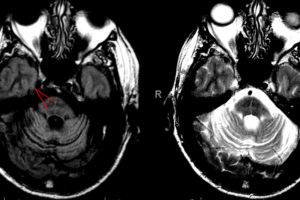

MSA hot cross buns sign